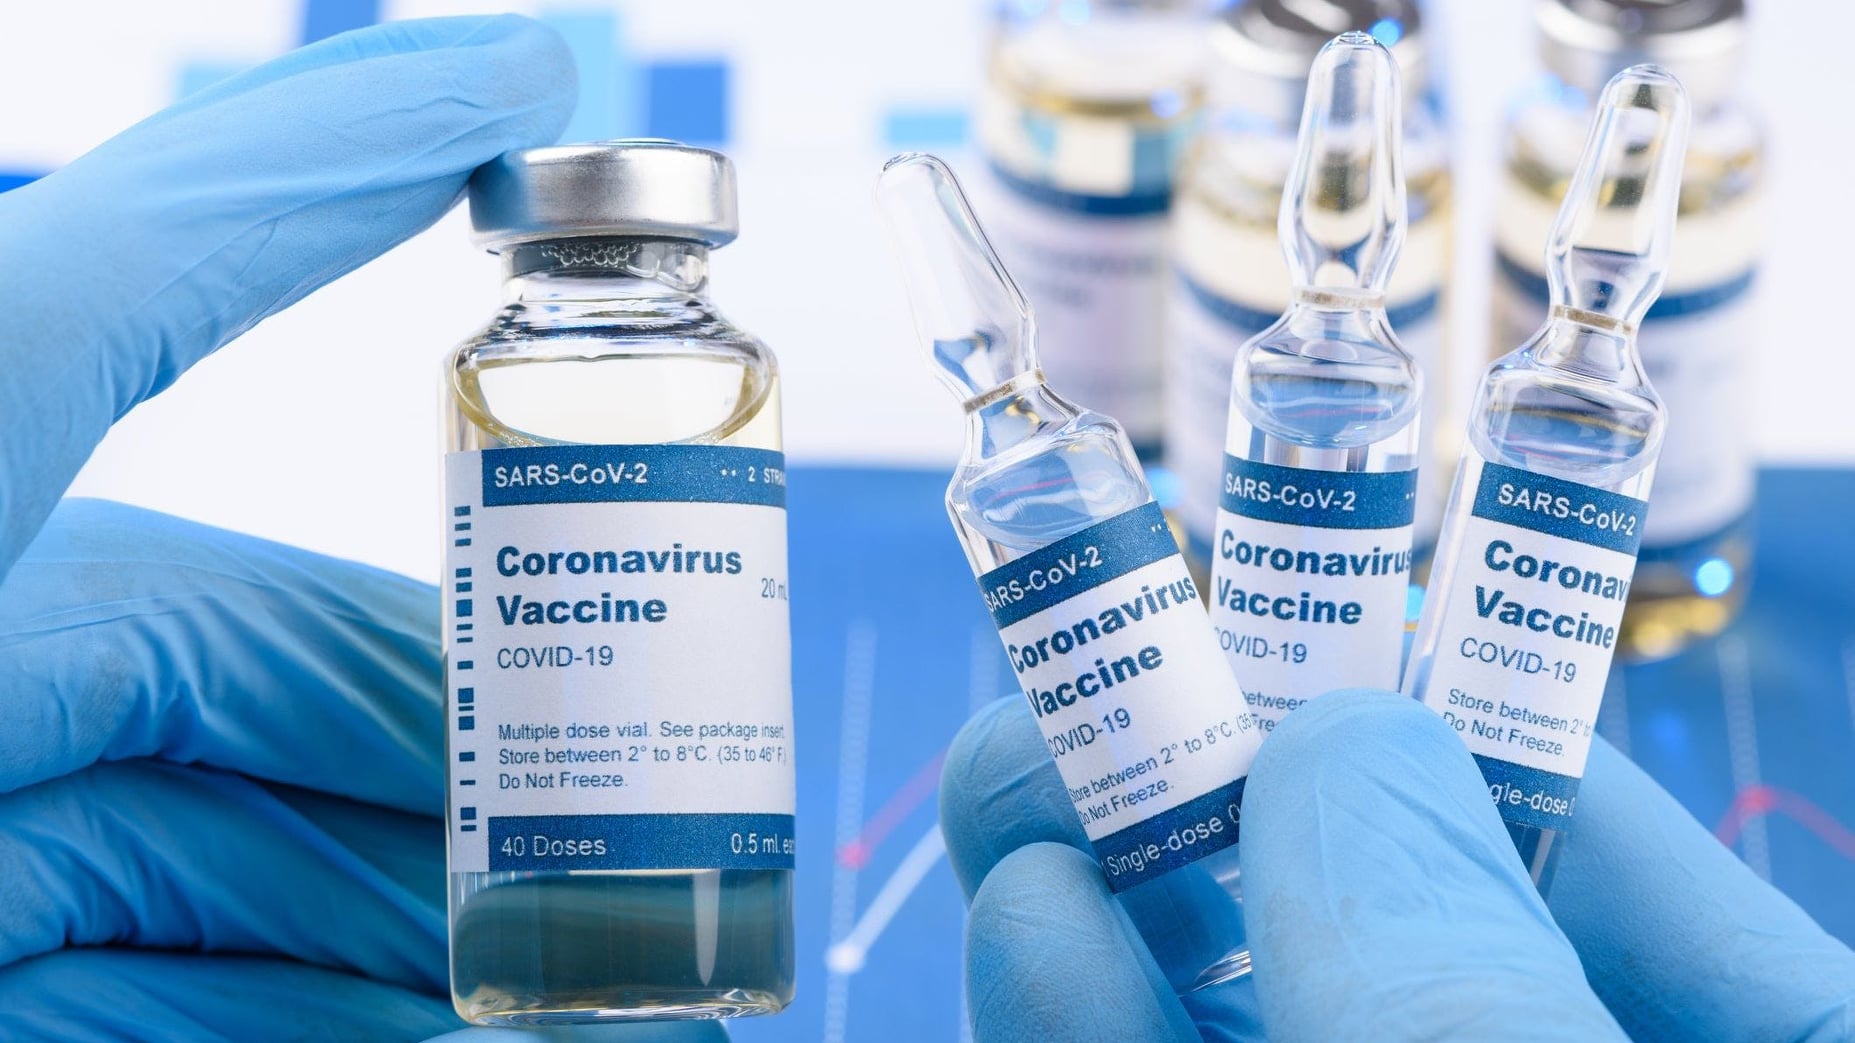

В Україні людям, які отримали бустерну дозу, даруватимуть знижку на поїздку в таксі

МОЗ: Уперше з початку пандемії було зроблено понад 100 тисяч ПЛР-досліджень за добу

Депутати Вараської міської ради виділили майже 2 мільйони для придбання тест-систем

Пів тисячі - у важкому стані, 9 жителів Рівненщини померли за добу від коронавірусу

Більше 3 тисяч випадків захворювання на коронавірус зафіксували в Україні за добу

COVID-19 на Рівненщині: 32 нових випадки, серед них 4 дітей, ще одна людина померла